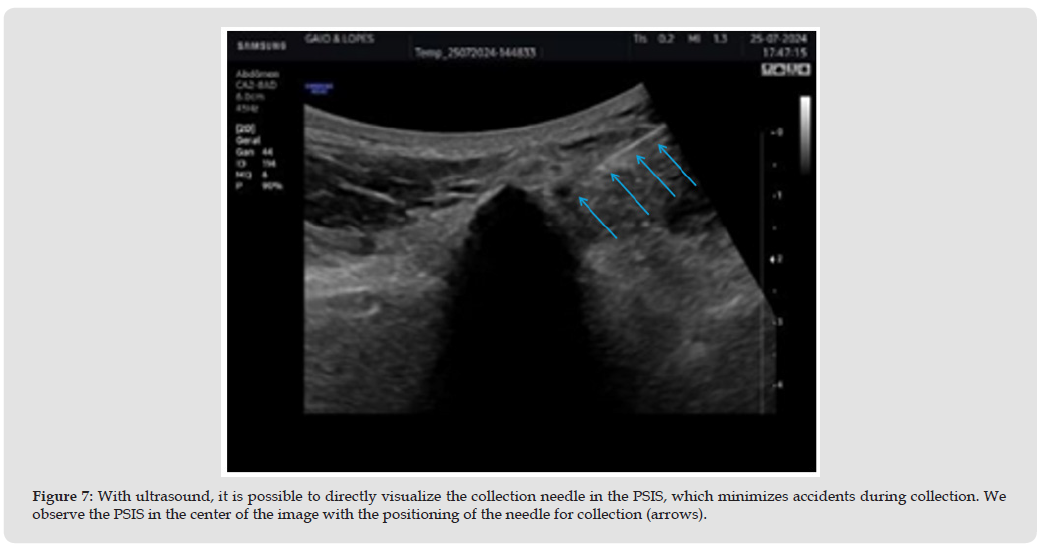

The sonoguided procedure tends to be less painful due to the precision of the puncture, resulting in less tissue trauma. Because it is a less invasive method, the post-procedure recovery time is usually shorter. Ultrasound visualization allows healthcare professionals to perform the procedure with more confidence and fewer attempts, increasing the overall efficiency of the collection [28,29,42-44] (Figure 7). Sonoguided collection of spinal cord aspirate in the posterosuperior iliac spine not only increases the success rate of the procedure but also provides greater comfort and safety to the patient. Ultrasound technology, with its ability to provide real-time images, revolutionizes the approach to these procedures, offering a modern and effective alternative that is confluent with the minimally invasive approaches used in the practice of regenerative medicine.